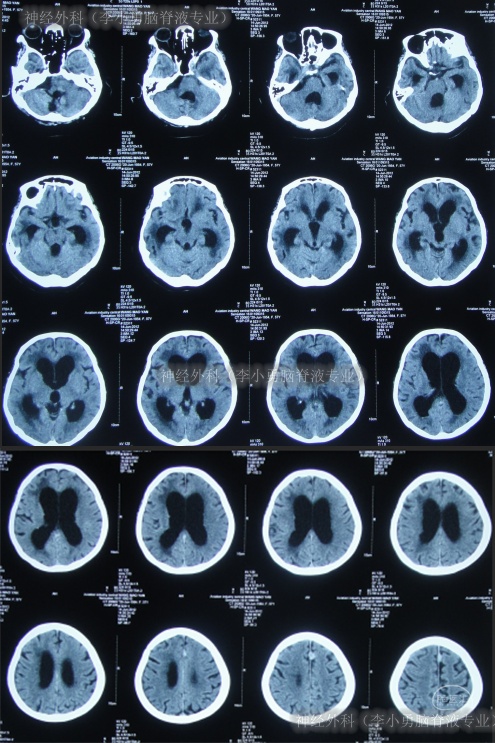

第2家医院出院1月余即2012年2月7日,夜里起夜突然又重复发作以前的症状(恶心呕吐、头昏),且比前2次发作严重,2012年2月8日住入第3家医院:呼和浩特市某三甲医院的神经外科治疗,入院查头颅CT(图-2)和MRI(图-3);脊髓核磁(图-4);肺部CT(图-5)及多次腰椎穿刺脑脊液化验检查(糖低、蛋白高),诊断为:结核性脑膜炎,脑积水。

图-2:2012年2月9日头颅CT

图-3:2012年2月9日头颅核磁